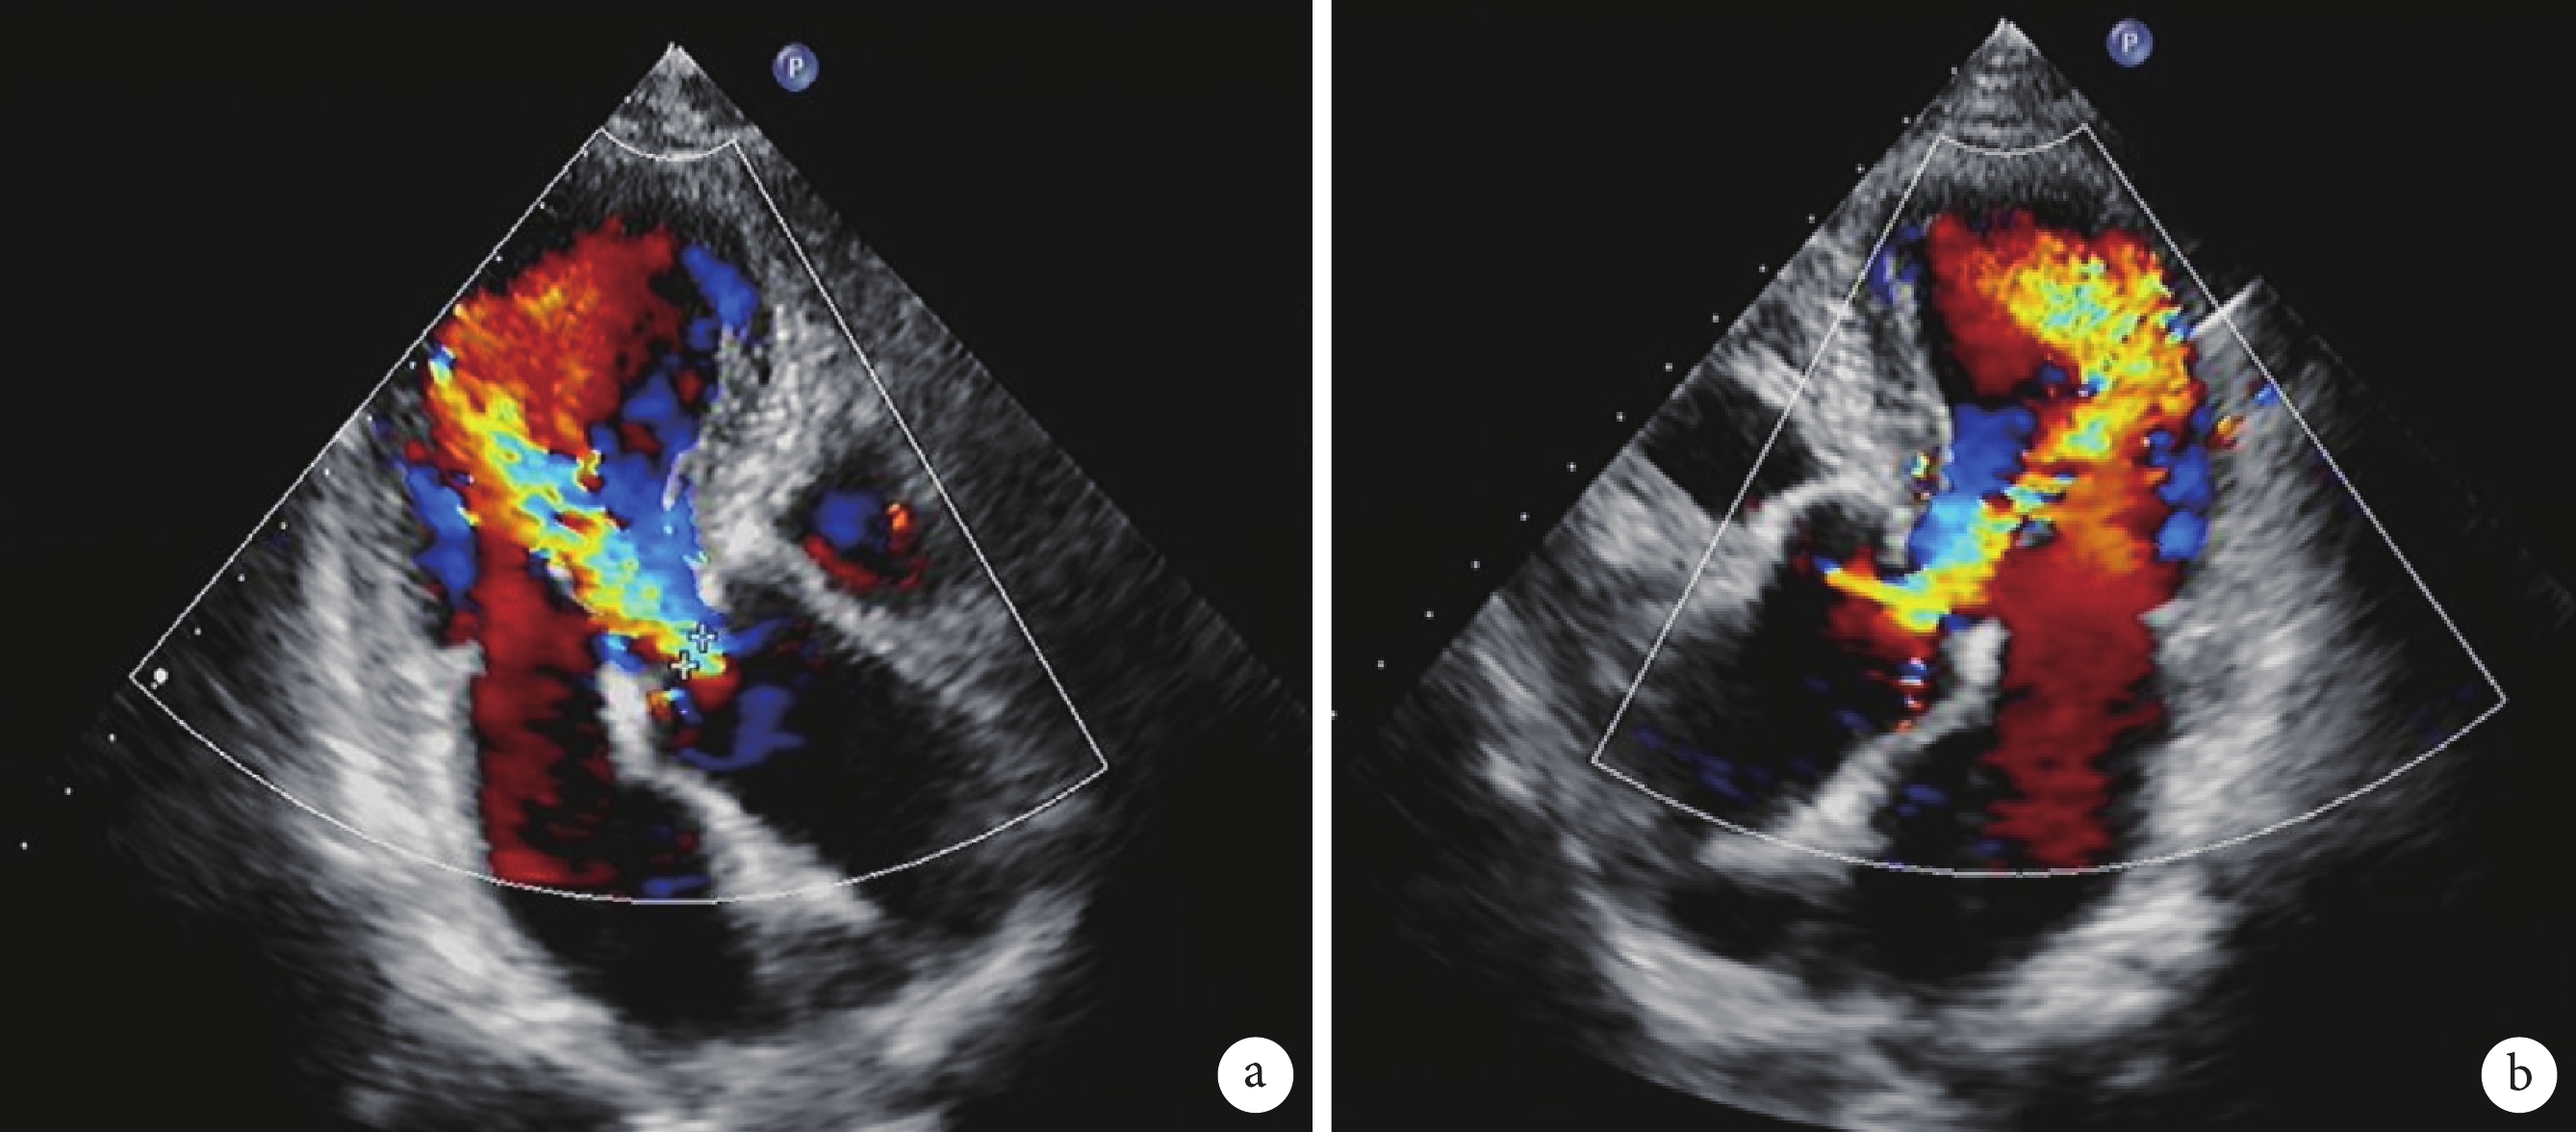

所有患者術前均行經胸超聲心動圖和MDCT檢查,超聲心動圖評估患者心功能、AR程度、瓣口面積及瓣壓差等;見圖1。通過荷蘭 PIE 醫學影像公司的 3MENSIO 軟件結合MDCT,對主動脈瓣環平面、瓦氏竇平面、竇管交界平面、左室流出道平面和升主動脈平面進行測量分析,并測量左、右冠狀動脈竇距主動脈瓣環的高度,評估患者主動脈根部解剖和入路形態;見圖2。經過TAVR團隊和心臟外科團隊共同討論認為手術具有可行性。

主動脈瓣重度反流、左室增大及升主動脈增寬